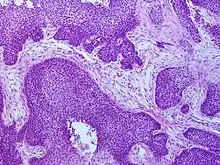

Diagnosis

Medical history, physical examination and medical imaging may suggest a squamous-cell carcinoma, but a biopsy for histopathology generally establishes the diagnosis. TP63 staining is the main histological marker for squamous-cell carcinoma. In addition, TP63 is an essential transcription factor to establish identity of the squamous cells.[16]